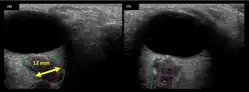

The astronauts affected by long term visual changes and prolonged intracranial hypertension have all been male, and SOS may explain this because in men, the sternocleidomastoid muscle is typically thicker than in women and may contribute to more compression. The reason that SOS does not occur in all individuals may be related to anatomic variations in the internal jugular vein. Ultrasound study has shown that in some individuals, the internal jugular vein is located in a more lateral position to Zone I compression, and therefore not as much compression will occur, allowing continued blood flow.